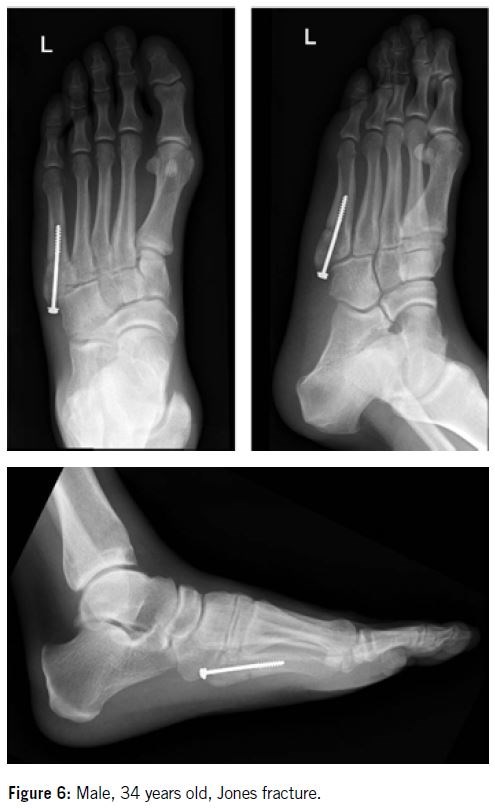

Beverly et al.6 showed that the lateral aspect of the forefoot was exposed to 78.6 N peak forces during normal weight bearing (Figure 6). The force leading to complete displacement of malleolar screws is on average 519 N, a much higher rate than the peak force experienced at the lateral aspect of the foot.

Pietropaoli et al.7 showed that the forces necessary to cause displacement of stabilized Jones fractures in their study are above the forces that should be transmitted within the lateral mid-foot during normal weight bearing. This suggests that the intramedullary fixation technique made no biomechanical difference in their study and is instead a matter of the surgeon's preference, as is the choice of screw (4.5 malleolar or 4.5 cannulated).

In 1975, Dameron2 was the first to suggest that athletes should undergo early operative treatment to prevent delayed union. Various surgical techniques have since been proposed, including intramedullary screw fixation, plating, percutaneous pinning, intramedullary curettage, and bone grafting (Figures 7 & 8). While the reported union rates with these methods are generally high, several complications have also been documented following their use.

Over the past 25 years, intramedullary screw fixation has emerged as the most widely used surgical technique for treating proximal fifth metatarsal diaphyseal fractures in athletes, with reports indicating improved union rates and faster recovery times. The partially threaded cannulated screw became the gold standard for operative treatment.

More recently, excellent bone healing outcomes have been reported with the use of headless compression screws. It is recommended to use the largest diameter screw that fits the width of the intramedullary canal, with a minimum diameter of 4 mm and a length of at least 50 mm. Proximally, the screw should be positioned to avoid irritation of the cuboid or the fourth/fifth intermetatarsal joint.

In 200512, we published our study detailing the operative treatment of 18 proximal fifth metatarsal stress fractures in 17 professional soccer players. Percutaneous intramedullary fixation using a 4.5 mm malleolar screw was performed in 11 athletes (Group I), while open intramedullary screw fixation combined with autologous cancellous bone grafting was used in the remaining seven (Group II).

Based on our experience, we recommend intramedullary screw fixation combined with autologous cancellous bone grafting as the primary surgical treatment for high-level athletes. To date, we have treated approximately 60 athletes using this technique, including four with bilateral proximal fifth metatarsal fractures. None of these cases resulted in refracture.